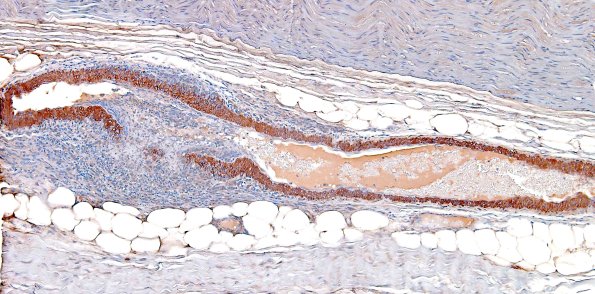

8B1,2 This is a longitudinal section of a large epineurial arteriole stained for smooth muscle actin. Notice that if cut in cross section at one level it would appear that the nerve was unaffected and at another level that the vessel was completely thrombosed. It is worth stressing that vasculitis may be focal along the nerve. (SMA IHC)